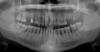

Nataly_34 Опубликовано 23 апреля, 2007 Поделиться Опубликовано 23 апреля, 2007 Уважаемые специалисты! Помогите разобраться в моем лечении пародонтита.Обратилась в стоматологам, потому что стали шататься зубы.Сделали полный снимок челюстей( наблюдается генерализированный уход тканей пародонта в нижней челюсти, в верхней в местах отсутствия зубов), провели профессиональную чистку зубов и чистку карманов системой Вектор. И затем предлагают различные методы лечения и протезирования. И здесь голова кругом и полная путаница.РАсскажу о способах по вариантам.1.Зашинировать всю нижнюю челюсть, передние шесть зубов верхней челюсти и поставить на отсутствующие зубы бюгелный протез.2.Сделать открытый кюретаж нижней челюсти. Затем удалить 2,3,5 зуб в правой части верхней челюсти и провести синус-лифтинг. Слева также синус-лифтинг с дальнейшей установкой имплантов. Однако иплантнты по стоимости потянуть очень тяжело и это очень долгий процесс.Может подскажете альтернативу имплантам.3.Предалагаю операции по подсадке костной ткани.Что вообще приводит в ужас.4.Еще были варианты проверок на остеопороз и половые гормоны.Мне 34 года. Еще в качестве информации осложнений со здоровьем особых нет.Имеется наследственная склонность к пародонтиту с обеих сторон. Подскажите пожалуйста, что действительно стоит сделать в таком потоке информации и как правильно подобрать план лечения.Снимок прилагаетсяЗаранее благодарна за ответы! Ссылка на комментарий

Bier Опубликовано 25 апреля, 2007 Поделиться Опубликовано 25 апреля, 2007 мне кажется по пункту 4 вам надо проверяться основательно.еще щитовидку проверьте. Я бы начал с комплексного обследования по всем специалистам. Уж очень печальная картина, и структура самой кости весьма рыхлая. Ссылка на комментарий

Bier Опубликовано 26 апреля, 2007 Поделиться Опубликовано 26 апреля, 2007 Док, на мой взгляд там именно парадонтоз, карманов практически нет, равномерная убыль костной ткани, и структура самой кости весьма рыхлая. Ссылка на комментарий